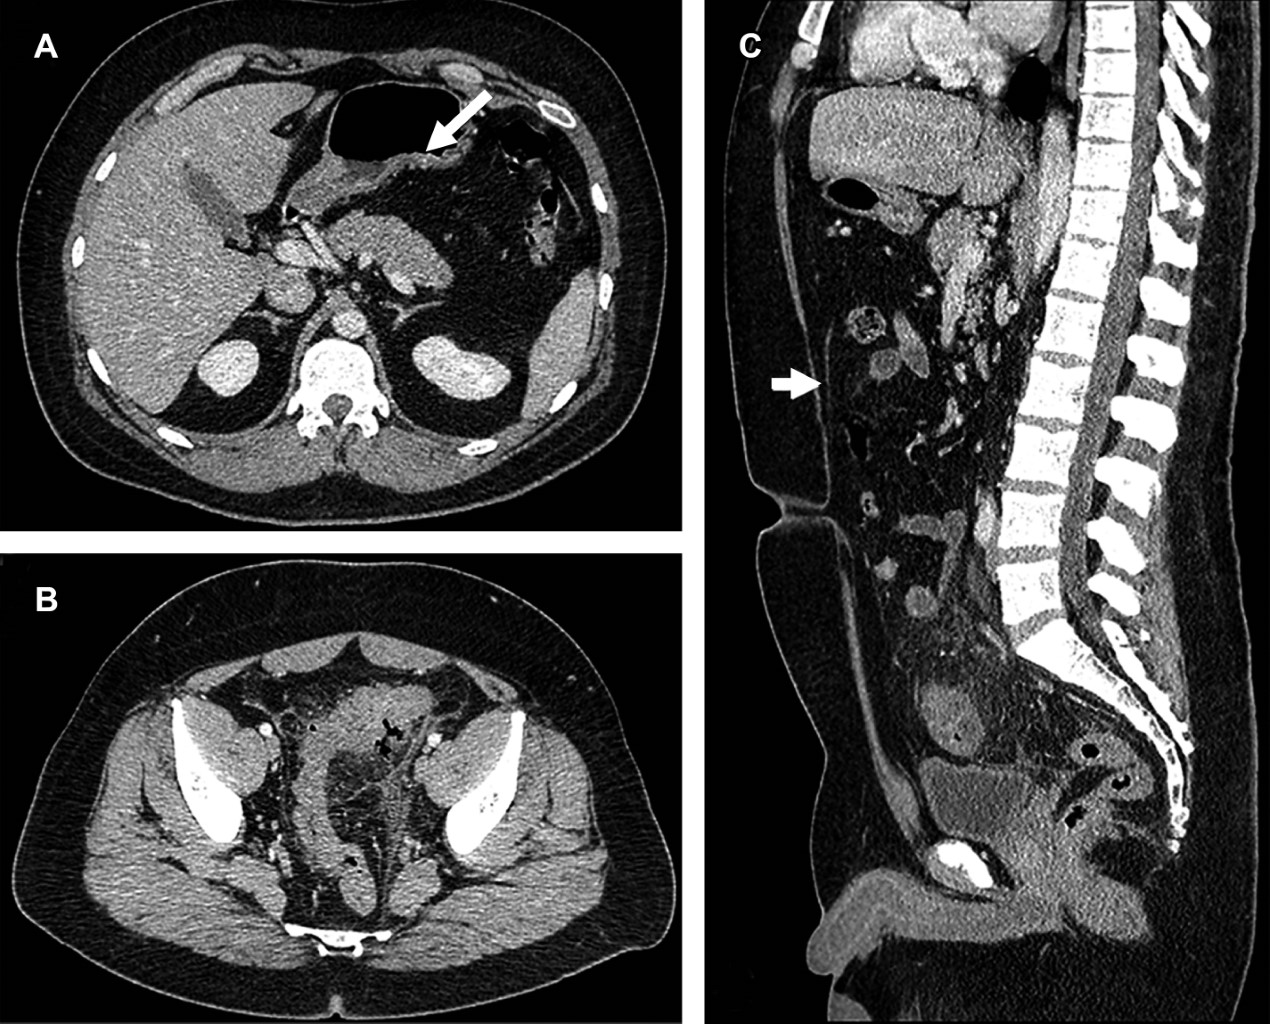

Se trata de paciente masculino de 34 años, inicia cinco días previo a su ingreso con dolor en fosa iliaca izquierda y dolor inguinal bilateral, acompañado de fiebre, escalofríos y diaforesis. A la exploración física a su ingreso presenta peristalsis disminuida, rigidez abdominal a la palpación y signo de Blumberg positivo. El laboratorio reportó: leucocitos de 15 × 109/L, hemoglobina de 15.6 g/dL, neutrófilos segmentados 11.54%, neutrófilos en banda 61%; examen general de orina (EGO): proteínas y cuerpos cetónicos presentes, leucocitos 2 × campo, bacterias escasas y sangre ausente. La tomografía computarizada abdominopélvica simple y con contraste IV mostró diverticulitis sigmoidea, Hinchey 1a (Figura 1). Cuatro días después manifiesta dolor abdominal irradiado a epigastrio, la tomografía de control simple y contraste IV (Figuras 2 y 3) mostró cambios inflamatorios en el recorrido completo del ligamento Teres, altamente sugestivos de trombosis, así como vesícula biliar reactiva (pared gruesa) y adenitis mesentérica, discreto líquido libre abdominal y derrame pleural bilateral. El paciente recibió tratamiento conservador y fue dado de alta al séptimo día.

Figura 1